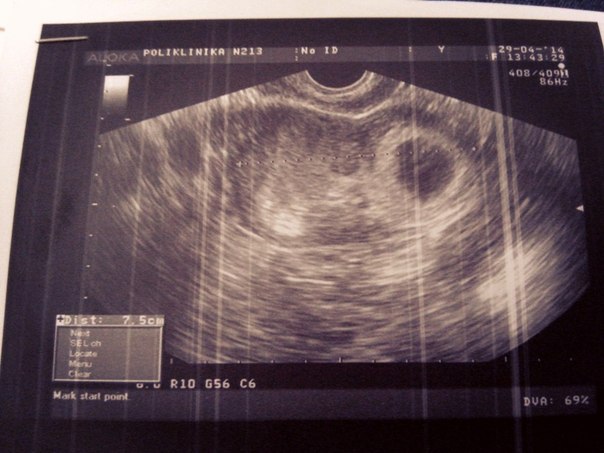

спасибо за поддержку) это первый снимок, а вот на последнем, т.е на пред последнем та тоже что то есть, но врач сказала что не понимае что, скорее всего замершая беременность(

А какой срок? По узи действительно пока пусто. Только хгч в динамике даст ответ

Александра

Плодное яйцо видно,но эмбриона я там не вижу.Я не врач,конечно.Но деформированное плодное яйцо не очень хорошо.А ХГЧ очень высокий.Вы к врачу ходили?К гинекологу?

Это по месячным? Если да, то у меня на этом сроке тоже эмбрион не видели. И тут много таких. Но у меня яйцо было недеформировано